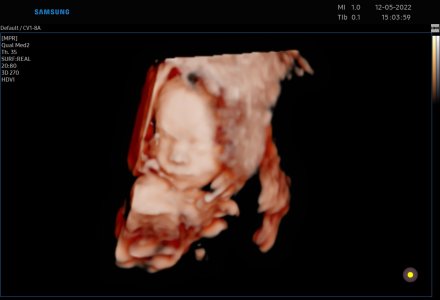

Těhotenství je fysiologickým dějem v životě ženy. Většina těhotenství probíhá bez komplikací, však část z nich se může komplikovat nepříznivým průběhem. Pečujeme o fysiologické těhotenství a snažíme se předvídat a v případě potřeby adekvátně zasáhnout u těhotenství rizikových dle doporučených postupů. V rámci péče o těhotné nabízíme vyhledávání genetických a vrozených vývojových vad plodu pomocí prenatální diagnostiky I. trimestru ( prvotrimestrální kombinovaný skríning- ultrazvukový i biochemický) , II. a III. Trimestru ( ultrazvukové vyšetření.).Nabízíme možnost zajištění v případě potřeby superkonziliárních ultrazvukových vyšetření, konzultační činnost. Provádíme 3D a 4D ultrazvukové vyšetření s možností záznamu.

- ultrazvuková diagnostika (možnost zápisu 3D/4D ultrazvuku , obraz v reálném čase), kardiotokografie